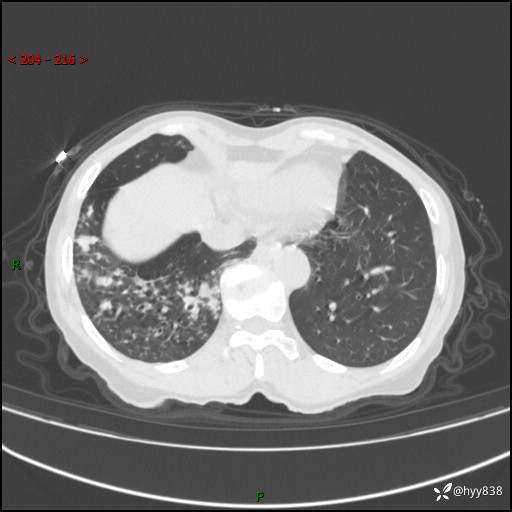

患者性别:男

患者年龄:69岁

简要病史:咳嗽咳痰2月,夜间加重

临床诊断:感染

胸部CT平扫